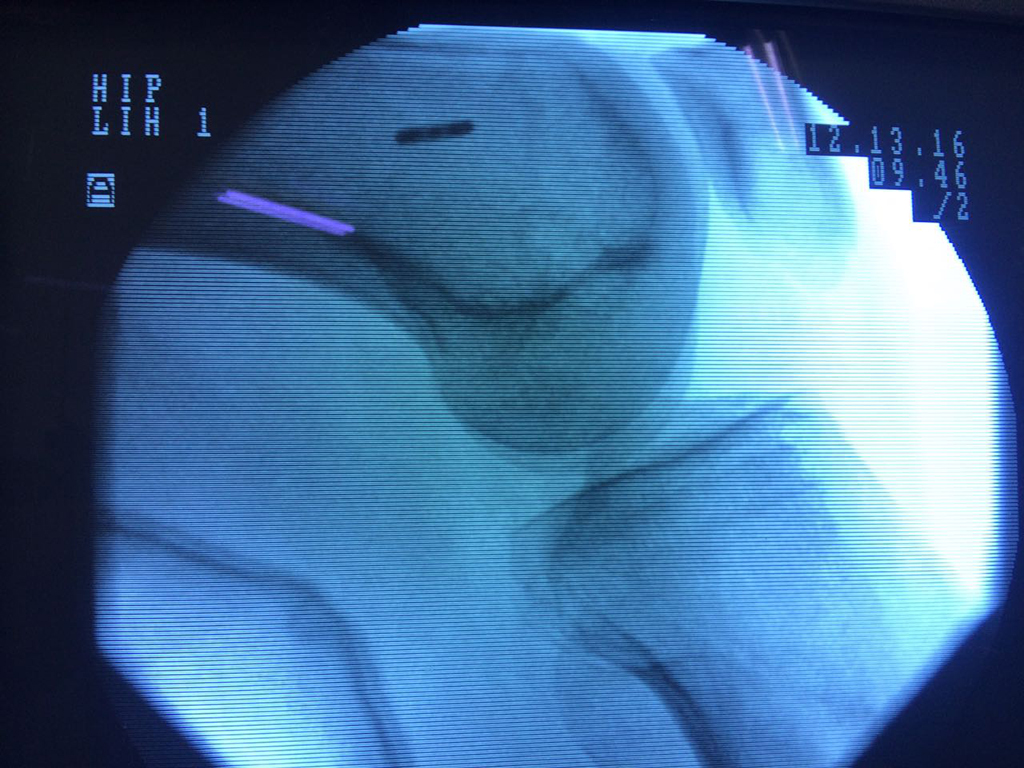

Cirugías de Cadera